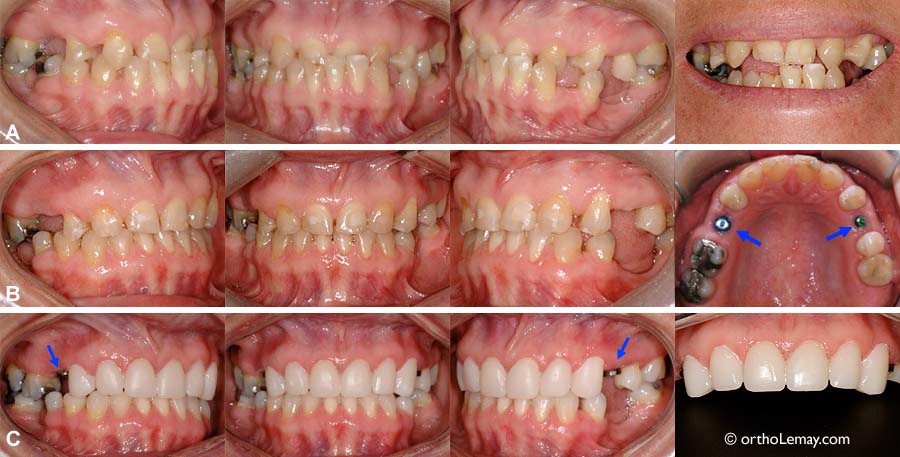

Caractéristiques du cas SM

(A) Pont joignant 4 dents (flèches). La canine est contre la centrale et le dentiste désire la déplacer à sa positon normale vers l’arrière en prévision de restaurations futures.

(B) Fin du traitement d’orthodontie. L’ancien pont a été coupé (flèche) pour permettre de reculer les dents et ouvrir un espace antérieur.

(C) Restaurations finales faites par le dentiste. Un nouveau pont et des couronnes ont été faits à l’arcade supérieure.